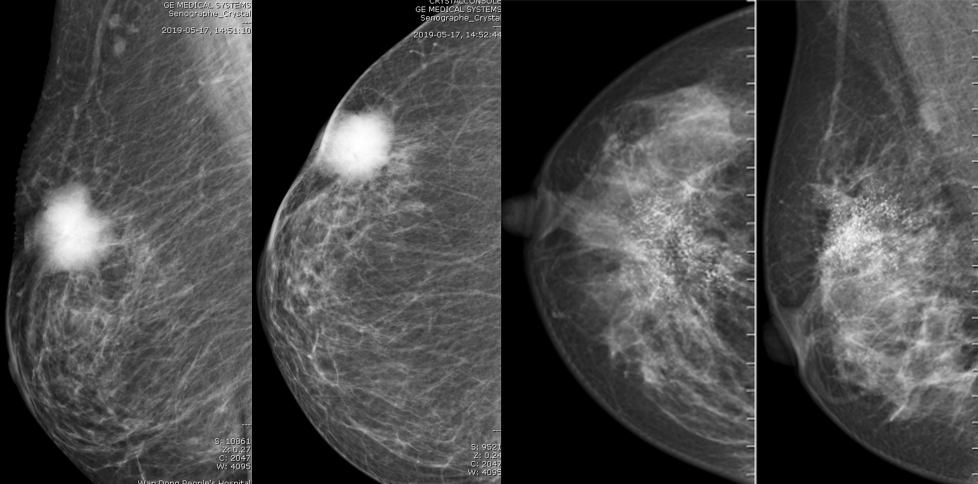

MG/CT:

乳腺炎:包括急、慢性乳腺炎和乳腺脓肿,多见于产后哺乳期妇女,急性乳腺炎常有典型的临床症状-红、肿、热、痛;若治疗不及时可形成慢性乳腺炎或乳腺脓肿。MG 表现片状致密影,边缘模糊,患处皮肤水肿增厚,皮下脂肪层模糊;MRI-T1WI 表现为片状低信号,T2WI 高信号,信号强度不均匀,边缘模糊,皮肤水肿、增厚,增强 MRI 通常表现为轻至中度强化,且以延迟强化为主。